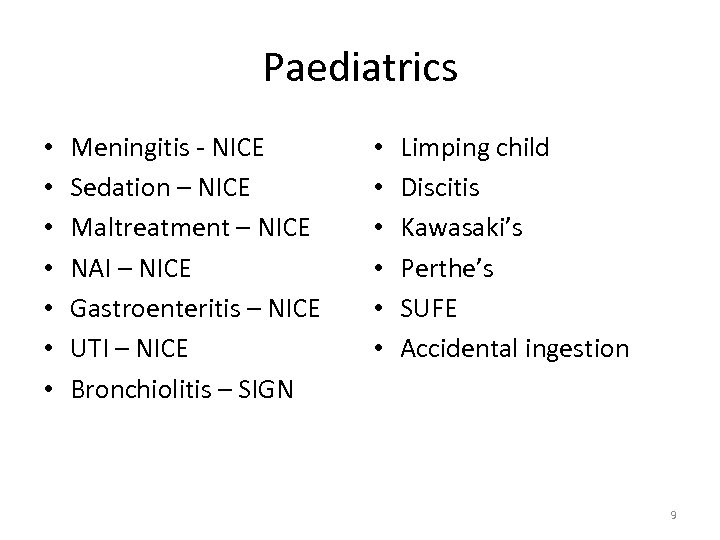

Paediatrics • • Meningitis - NICE Sedation – NICE Maltreatment – NICE NAI – NICE Gastroenteritis – NICE UTI – NICE Bronchiolitis – SIGN • • • Limping child Discitis Kawasaki’s Perthe’s SUFE Accidental ingestion 9